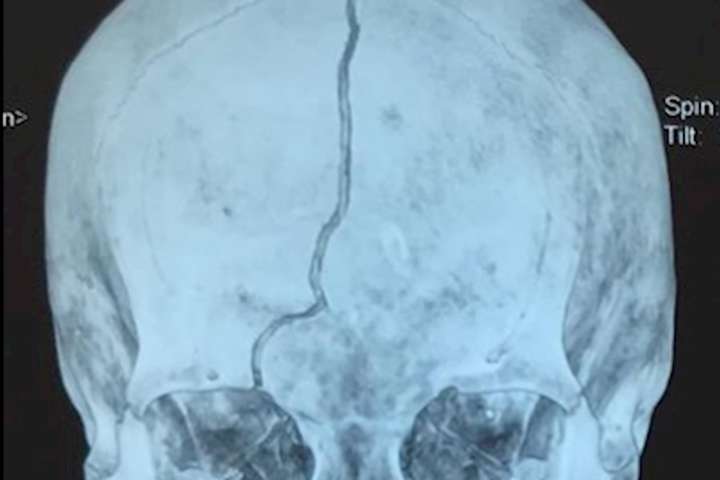

Бабуся зараз в реанімації, вона знаходиться в комі після важкої черепно-мозкової травми

«Нелюдь зробив це за копійчаний телефон і 100 гривень в гаманці у бабусі. Бабуся зараз в реанімації, вона знаходиться в комі після важкої черепно-мозкової травми. Шансів на те що виживе дуже небагато», - розповів він.